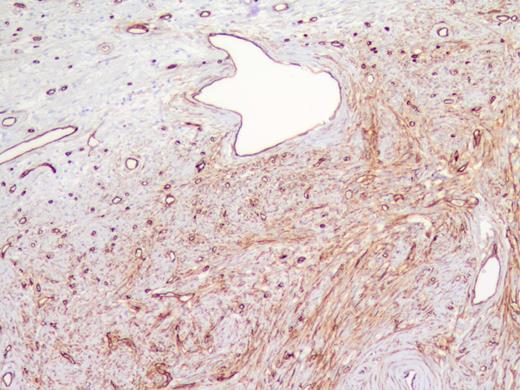

The specimen was a 3.5 ×3 ×3-cm white, firm, well-circumscribed mass located in the head of the pancreas (Fig. 3). The mass was found to be compressing the distal aspect of the main pancreatic duct. All 15 lymph nodes received in the specimen were negative. Histologically, the tumor is well circumscribed from normal pancreatic tissue and composed of spindle cells that in some areas form short ill-defined fascicles and in other areas are randomly arranged in a dense fibrohyaline stroma. A well-developed vascular network was visualized throughout the tumor with vessels of a stag horn appearance with thin hyaline wall and tumor growth around (Figs 4 and 5). No significant mitotic activity or tumor necrosis was noted. Immunostaining was positive for CD34 (Fig. 6) and BLC-2; focally for B-catenin, and focally weak staining for CD99, compatible with fibroblastic origin. The tumor cells were negative for the following cell markers: CD117, CAM5.2, AE1/AE3, EMA, synaptophysin, chromogranin, CD56, PR, SMA, Desmin, S100, MelanA and HMB45. The M1B1 proliferation index was low (<5%). These findings in combination are consistent with a SFT.

These tumors are difficult to distinguish radiologically from endocrine tumors as they appear hypervascular and well circumscribed on CT scan. The mainstay of diagnosis is histological. Particularly, the growth pattern and immunochemistry are helpful in differentiating SFTs from other mesenchymal tumors. These tumors tend to demonstrate spindle cells that grow in patternless arrangements with varying amounts of collagen and that stain positive for the cell markers CD34, CD99 and BCL-2.